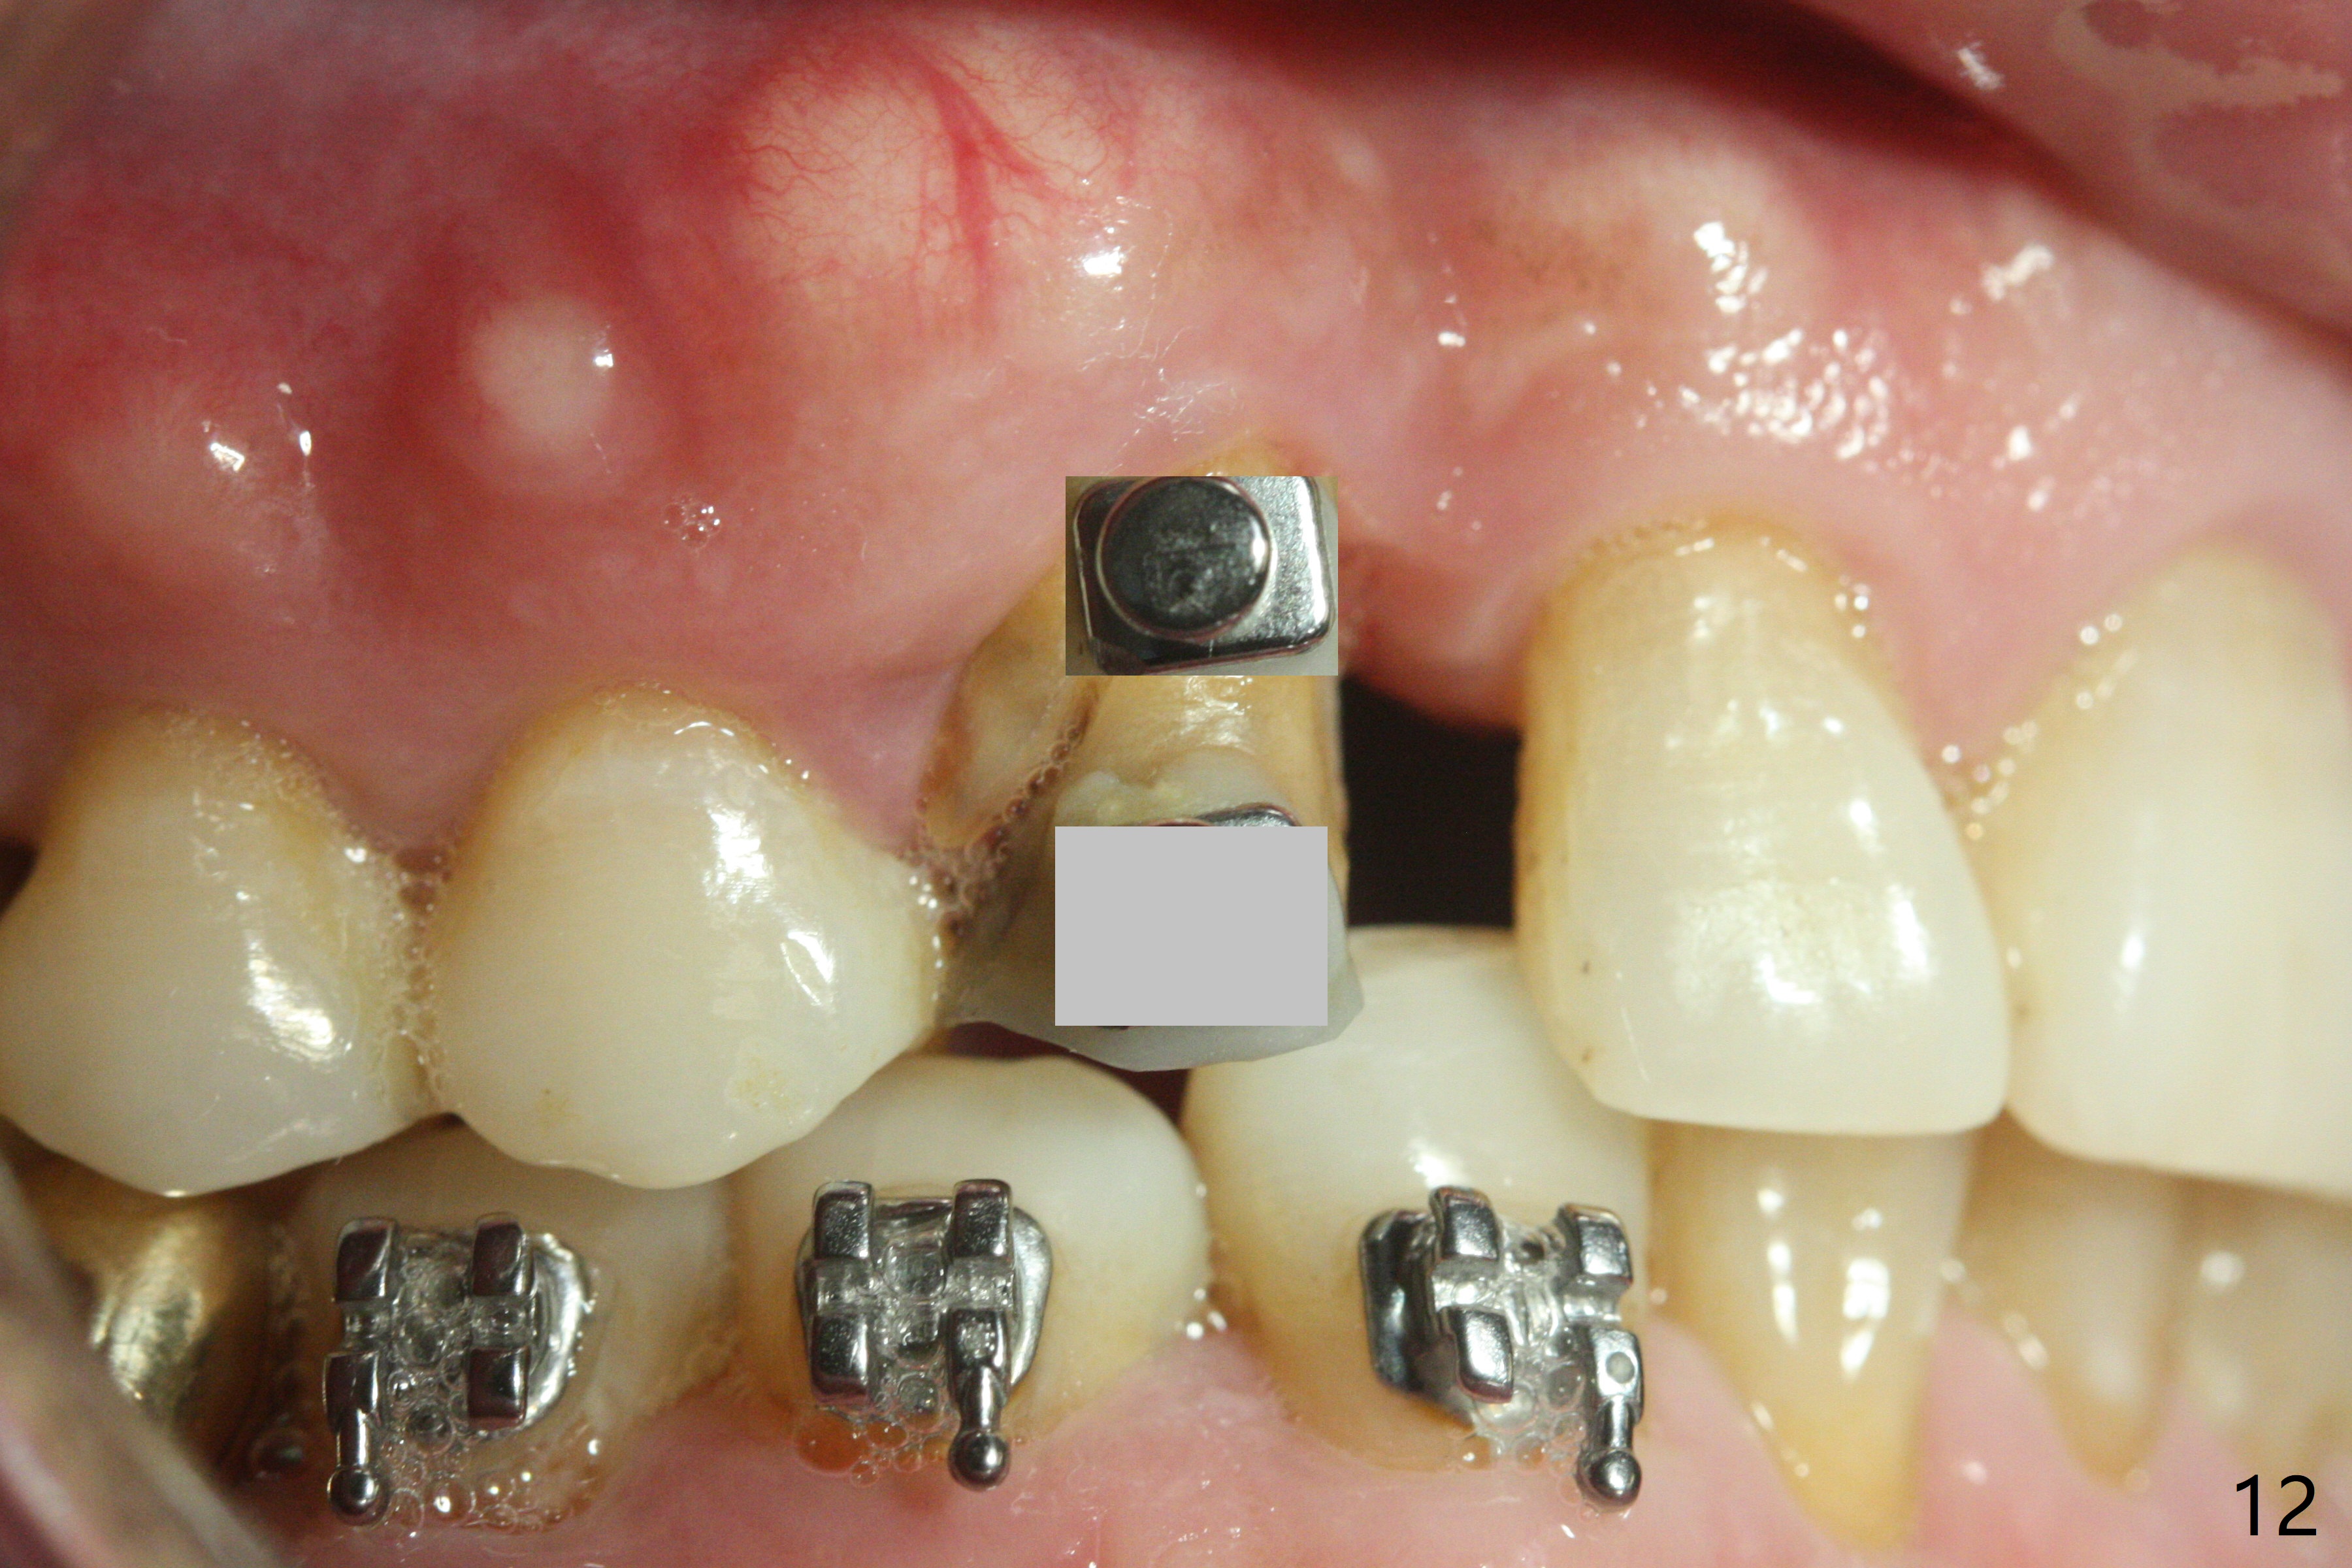

A 62-year-old man had traumatic root fracture at #6 in his teen. The tooth remained asymptomatic until his fifties. Following root canal therapy (Fig.1), the tooth is orthodontically extruded (~ 5 years, Fig.2 (*: bracket)) with apparent disappearance of the infection. The bone distal to #7 seems to increase in height (Fig.3, as compared to Fig.1) and in density (Fig.4). Bone graft could be placed for regeneration with PRF or GEM21S (Fig.5 red (between #6 and 7), pink (buccal to #7 or coronal to the fracture line) circles). With extrusion, the oblique fracture line is more than half or two third supragingival (Fig.6). In spite of severe bone loss, exostosis is present (Fig.7 (mesiobuccal view) E) so that bone graft could be placed palatal to it (Fig.8 red). In case the tooth is non-salvageable, immediate implant will be placed with guide (Fig.9,10). Move lingual button as apical as possible (Fig.12) and make occlusal clearance. Continue extrusion until all of the crack is exposed without deep pocket.